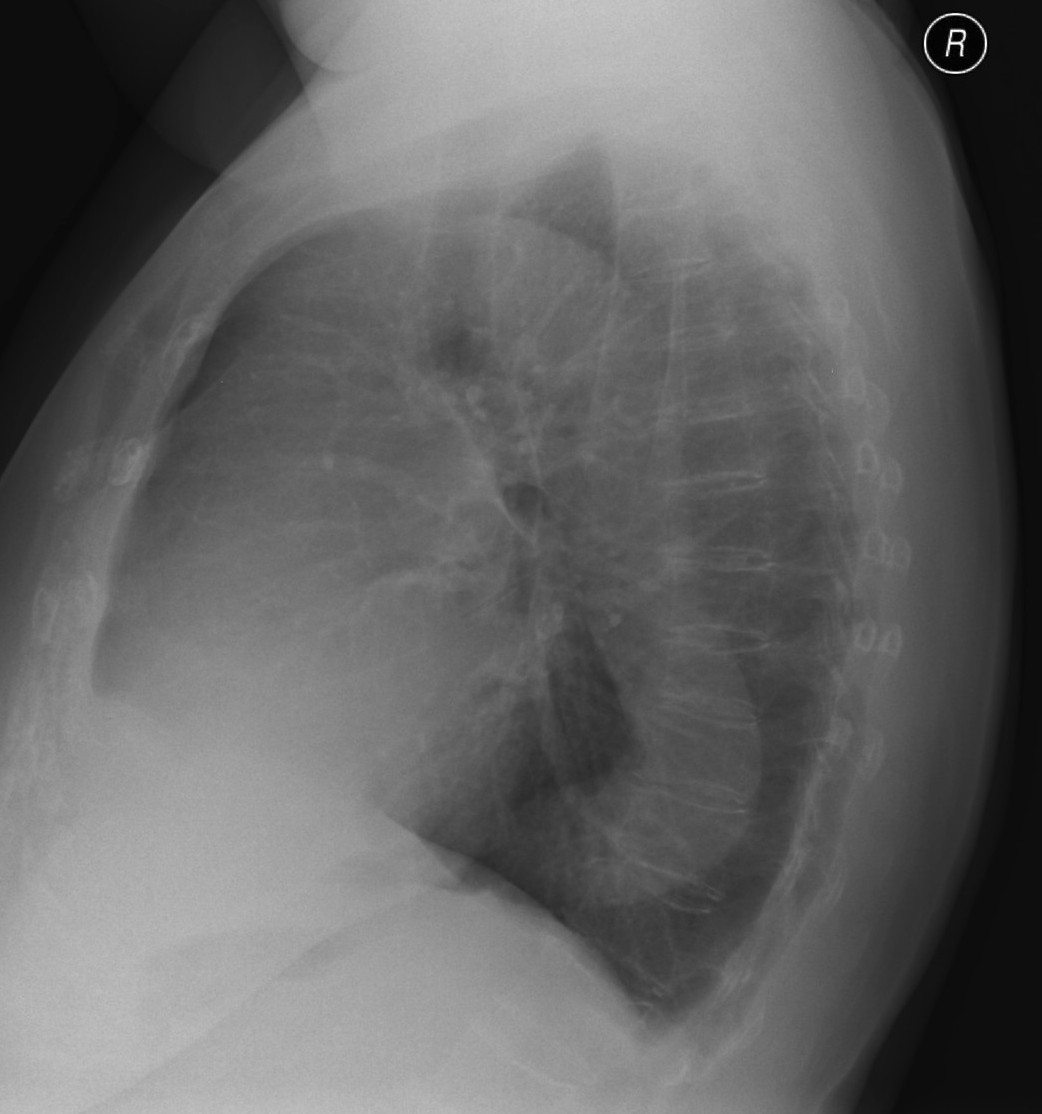

23. Pulmonary metastases, bidirectional (PA and right lateral) plain chest radiograph.

51 year old woman, endometrial carcinoma. Numerous ring shadows bilaterally in basal dominance (max. appr. 12 mm). Left pleural effusion of one finger wide.